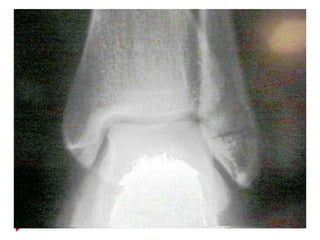

Valoración radiográfica

   SUPERPOSICIÓN TIBIOPERONÉA(la situación

posterior del peroné con relación a la tibia determina que

al tomar los Rx AP se observe sobreposición de los dos

huesos)

   > 10 mm

   < Lesión de la SINDESMOSIS (permite que se abra la mortaja

tibio-peronéa)

   CLARO TIBIO-PERONÉO (Espacio existente entre el

borde medial del peroné al nivel de la

sindesmosis, a 1 cm por arriba del maleolo de la

Tibia)

   < de 5 mm - 6 mm

   Angulo talo-crural – es el ángulo existente entre

una línea paralela a la superficie articular del

―plafón‖ tibial y otra línea que una los puntos más

distales de los dos maléolos. Este ángulo refleja la

diferencia de longitudes del maléolo externo y

medial y su valor oscila entre los 8 y los 15 grados.

Cuando el valor es menor se debe sospechar

acortamiento del peroné por fractura en el mismo.